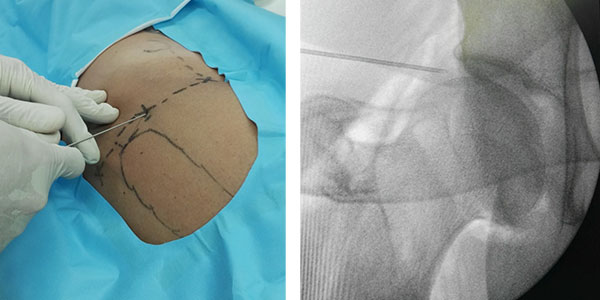

• Acido hialurónico

El AH es un componente viscoelástico importante del líquido sinovial presente dentro de las articulaciones con propiedades de amortiguación y lubricación. En ciertas afecciones la concentración y el peso molecular de AH disminuyen, perdiendo sus propiedades. Numerosas publicaciones sugieren que el uso de AH articular es una buna opción terapéutica para paciente con artrosis leve.

AH

cadera